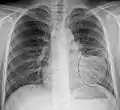

Normal AP CXR

Normal lateral CXR

AP CXR showing left lower lobe pneumonia associated with a small left sided pleural effusion

AP CXR showing right lower lobe pneumonia

AP CXR showing pneumonia of the lingula of the left lung

Right upper lobe pneumonia as marked by the circle.

Left upper lobe pneumonia with a small pleural effusion.

Right lower lobe pneumonia as seen on a lateral CXR